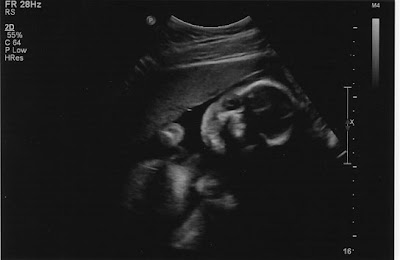

As a surprise we were shown 3D images. The sonographer was trying to be nice and get us a good face shot and Zakumi chose not to cooperate. At first with one fist in front of the face, then with two. There was a lot of tapping on my belly, and each time my babe waved fist like (s)he was getting ready for a fight. Scrappy little baby, like a Pikey from the movie Snatch.

Finally the sonographer backed off and we were able to see some face.

This was the best image. As an added bonus it looks like the baby may look more like me than my husband. Oh boy, but that is a different story. It is funny when both of your parents are so different looking. My husband and I have been super curious what this baby would look like.